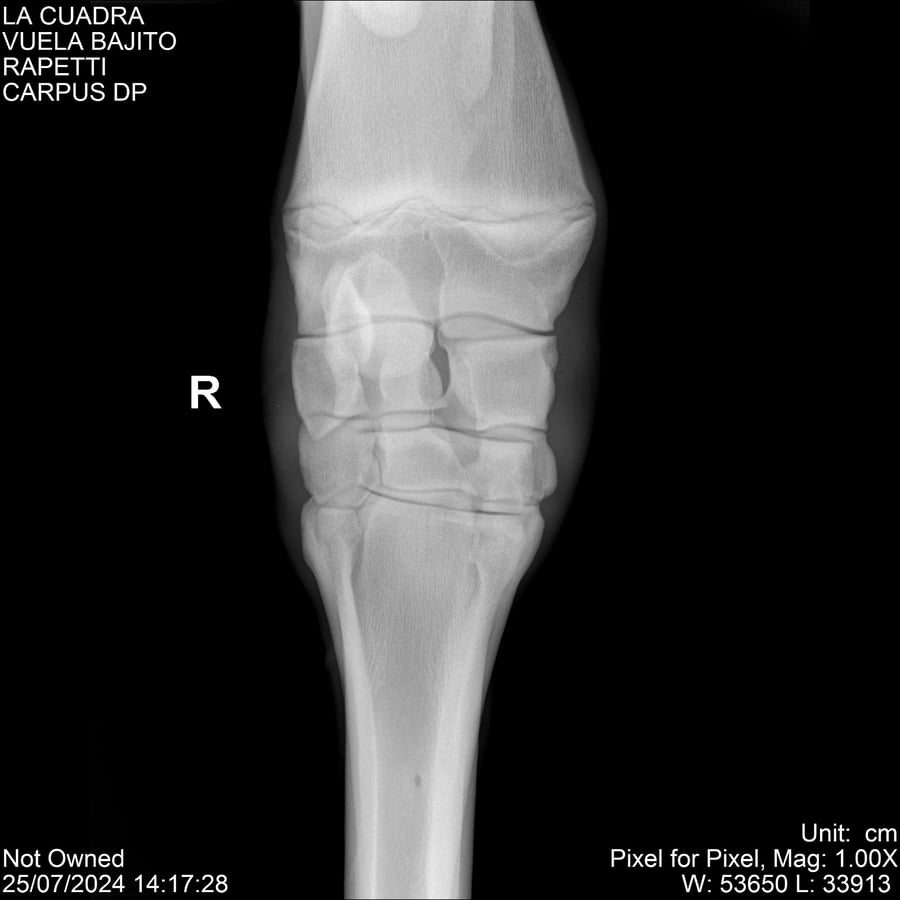

LOTE 16, VUELA BAJITO Lote Anterior Volver al remate Lote Siguiente Ficha Contacto Montevideo - Ficha del Lote Identificador: #284451 Categoría: Yeguarizos Montevideo - 77 Visualizaciones ClicData Contacto Empresa: Abelenda N. R., Walter Hugo Nombre*: Teléfono* : E-mail* : Mensaje Enviar Registrese gratis Este contenido Exclusivo está disponible sólo para usuarios registrados Ingresar